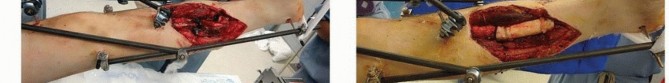

Monolateral Four-Pin Frame Application for Tibial Shaft Fracture Contemporary simple monolateral fixators have clamps that allow independent adjustments at each pin-bar interface, allowing wide variability in pin placement, which helps to avoid areas of soft tissue compromise. Because of this feature, simple four-pin placement may be random on either side of the fracture. ### Option 1 The initial two pins are first inserted as far away from the fracture line as possible in the proximal fracture segment and as distal as possible in the distal fracture segment ( TECH FIG 2A). A solitary connecting rod is attached close to the bone to increase the rigidity of the system. Longitudinal traction is applied and a gross reduction is achieved ( TECH FIG 2B-F). The intermediate pins can then be inserted using the pin fixation clamps attached to the rod to act as templates with drill sleeves as guides. These pins should not encroach on the open wound or severely contused skin in the immediate zone of injury. After placement of these two additional pins, the reduction can be achieved with minimal difficulty by additional manipulation of the fracture. Once satisfactory reduction has been accomplished, the clamps are tightened and reduction is confirmed via fluoroscopy. ### Option 2 Alternatively, all the fixation pins can be inserted independent of each other, with two pins proximally and two pins distally ( TECH FIG 3). The two proximal pins are connected to a solitary bar and the distal two pins are connected to a solitary bar. Both proximal and distal bars are then used as reduction tools to manipulate the fracture into alignment. Once reduction has been achieved, an additional bar-to-bar construct between the two fixed-pin couples is connected. Reduction is confirmed under fluoroscopy. 538

### TECH FIG 2 • Placement of a simple four-pin monolateral fixator. A. Two pins are placed on either side of the fracture as far from the fracture as possible. A connecting bar is then attached to the two pins (B) and a gradual reduction is performed (C-F). Two pins are then placed as close to the fracture as possible on either side, after longitudinal traction has accomplished a reduction. The inner pins are then attached, and the reduction is fine-tuned. 539

### TECH FIG 3 • Alternative method for simple four-pin monolateral fixator. A,B. Once the bar is attached, two intercalary clamps can be positioned as templates for the placement of the interior pins. C. Final construct after interior pin placement. D. The proximal and distal two pins can be attached to each other by a solitary bar. These bars can then be used as tools to reduce the fracture. E. The two bars are then connected by a solitary bar, and the fracture reduction is maintained. F,G. Closed fracture with associated compartment syndrome is reduced and stabilized using a four-pin fixator with a double stack bar for stability, and the foot is spanned to maintain a plantigrade foot. H. Similar tibial fracture reduced with four pins and a single bar. Note pins out of plane to each other to facilitate ease of pin insertion.